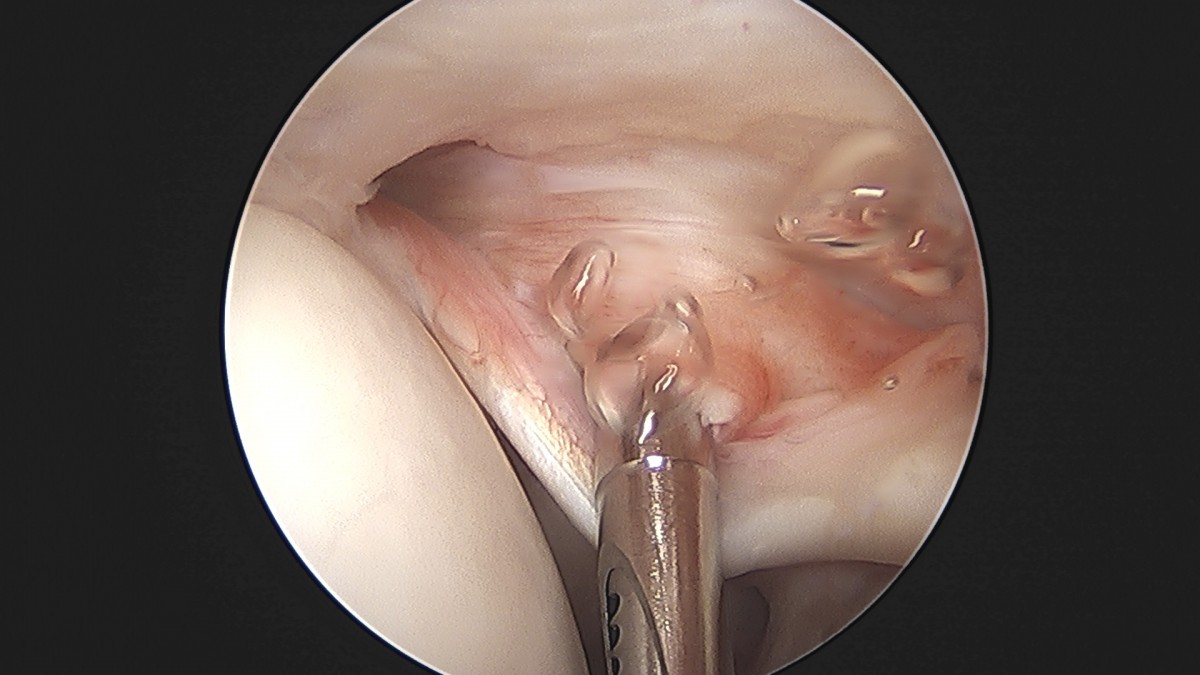

정지영원장님 어깨 관절낭 이완술 이상O 환자

dae765e4d9ac96aee867c9d6292d8784_1758009480_5047.jpg